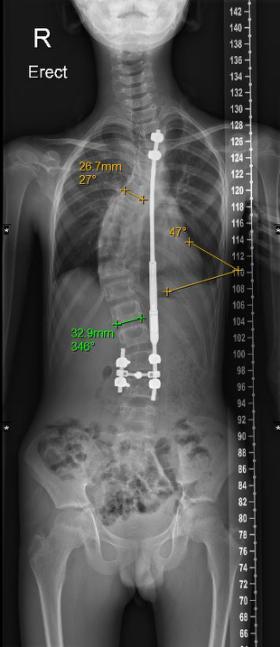

小磊手术前评估(左图),Cobb角度为61度,术后(右图)约为30度

在张文智教授团队及多学科共同合作下,小磊于5月3日进行了手术,手术时长约3小时,Cobb角由术前61度矫正为30度,手术进行得非常成功,“后续小磊只需要每2-3个月定期复诊一次即可。预计在植入的1-2个月后可撑开钛棒,并在未来三年内定期通过仪器进行体外拉伸,调整钛棒长度及脊柱角度,直到基本痊愈。”